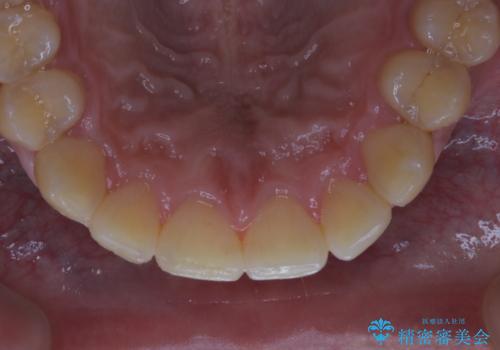

数年ぶりに歯のクリーニング(PMTC)

- しばらく歯科へ行っていなかったため綺麗にクリーニングしたいとのことでした。全体的に汚れが付着していたためPMTC60分コースを行いました。